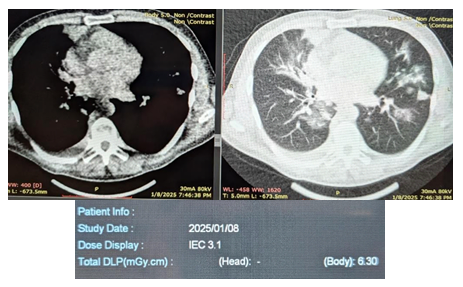

This technique shows promise for broader clinical application, particularly given the low effective dose range of 0.011–0.8 mSv achievable with ULDCT, which is well below the effective dose of conventional chest CT. Enhanced by modern dose-reduction methods like current modulation and iterative reconstruction, ULDCT may serve as a practical and safer imaging option for patients requiring frequent follow-up scans (Figure 1).1-3

Figure 1 ULDCT, with a radiation dose comparable to CXR.